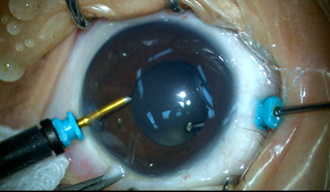

2006年,眼耳鼻喉科医院在国内首创微创玻切治疗先天性白内障,获教育部和上海市科技进步二等奖